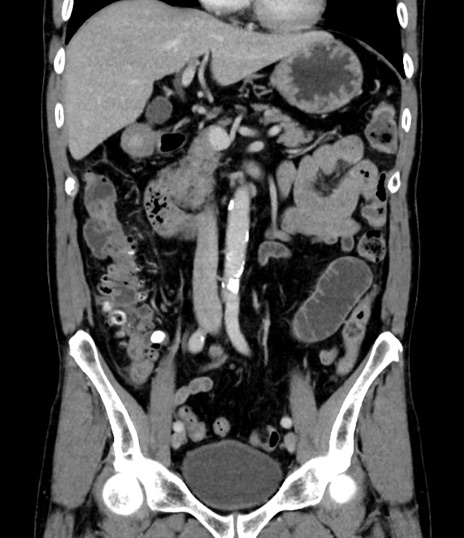

横断像

【症例】 60歳代男性

【主訴】 黒色吐物

【現病歴】 4日前から嘔気自覚、2日前の朝食後にも嘔気あり、自分で手で嘔吐反射起こし嘔吐したところ血が混ざっていたため受診。

【既往歴】 5年前汎発性腹膜炎を伴う急性虫垂炎で手術、高血圧、前立腺肥大症、高脂血症

【身体所見】 腹部正中に手術癩痕あり 腹部平坦・軟圧痛なし膨満感あり

【データ】WBC 8400、CRP 4.54